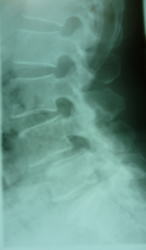

円背と腰痛症

円背が見受けられます 胸椎の代償作用として腰仙角が増大する人と少なくなる人と2通りあります。

胸腰部の圧迫骨折又は遺伝的要素もあり手技療法一番苦労します。

腰痛症で膝の痛み・肩こりも伴います。

いずれにしても少しでも胸椎と腰椎の柔軟性の回復が重要だと思われます。